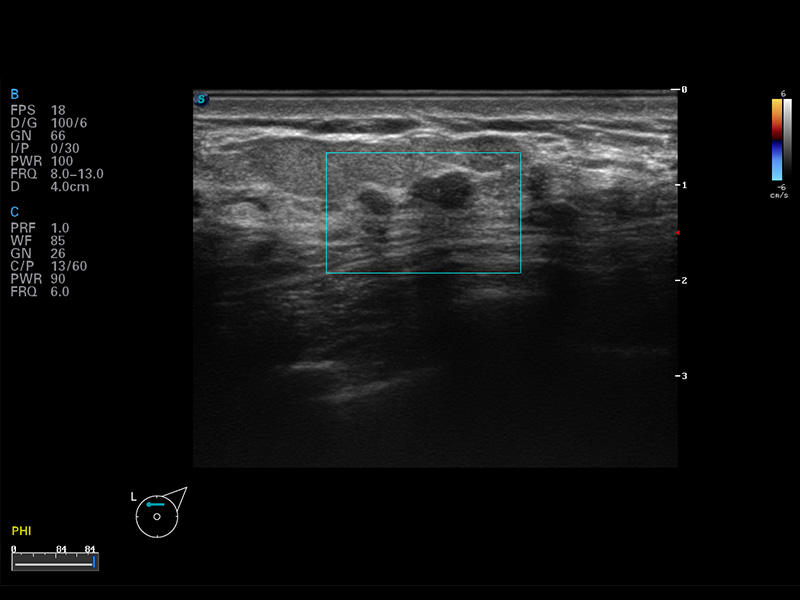

便携式彩色多普勒超声诊断仪

S8 EXP便携式彩色多普勒超声诊断仪是玖鼎集团研发的高端全身应用型便携彩超。高通道的VIS平台融合可视化(Visual)、智能化(Intelligent)和人性化(Smart)的特点,配以玖鼎集团自主研发生产的探头大家族,使您能够快速、准确的获得病人信息,提高工作效率的同时减轻疲劳。